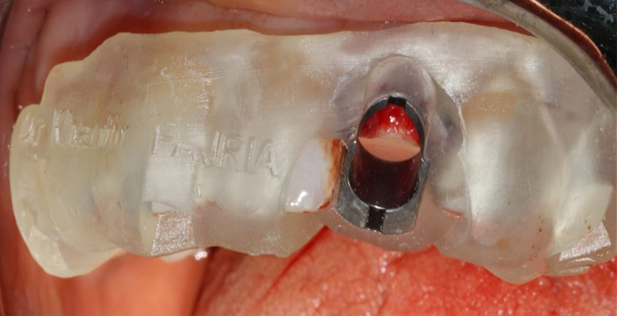

PMMA resin was placed around the provisional abutment, and the occlusion was checked to ensure that the provisional prosthesis was underbite (Figure12).

Figure 9. Drilling sequence

Figure 12. Placement of PMMA resin and final result of provisional prosthesis